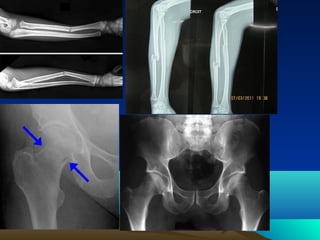

GPH XÖÔNG CHI DÖÔÙI

- Xöông      (2) + Xöông                 Ñai chi döôùi

chaäu            cuøng

- Xöông ñuøi                     Khôùp

- Xöông chaøy               Khôùphoâng

goái

- Xöông maùc

- Xöông baùnh

-cheø xöông coå chaân

Caùc

(7)

- Caùc xöông baøn   - Caùc xöông ñoát baøn

chaân (19)          chaân (5)

- Caùc xöông ñoát ngoùn chaân

(14)

GPH XÖÔNG CHIDÖÔÙI - Xöông (2) + Xöông Ñai chi döôùi chaäu cuøng - Xöông ñuøi Khôùp - Xöông chaøy Khôùphoâng goái - Xöông maùc - Xöông baùnh -cheø xöông coå chaân Caùc (7) - Caùc xöông baøn - Caùc xöông ñoát baøn chaân (19) chaân (5) - Caùc xöông ñoát ngoùn chaân (14)